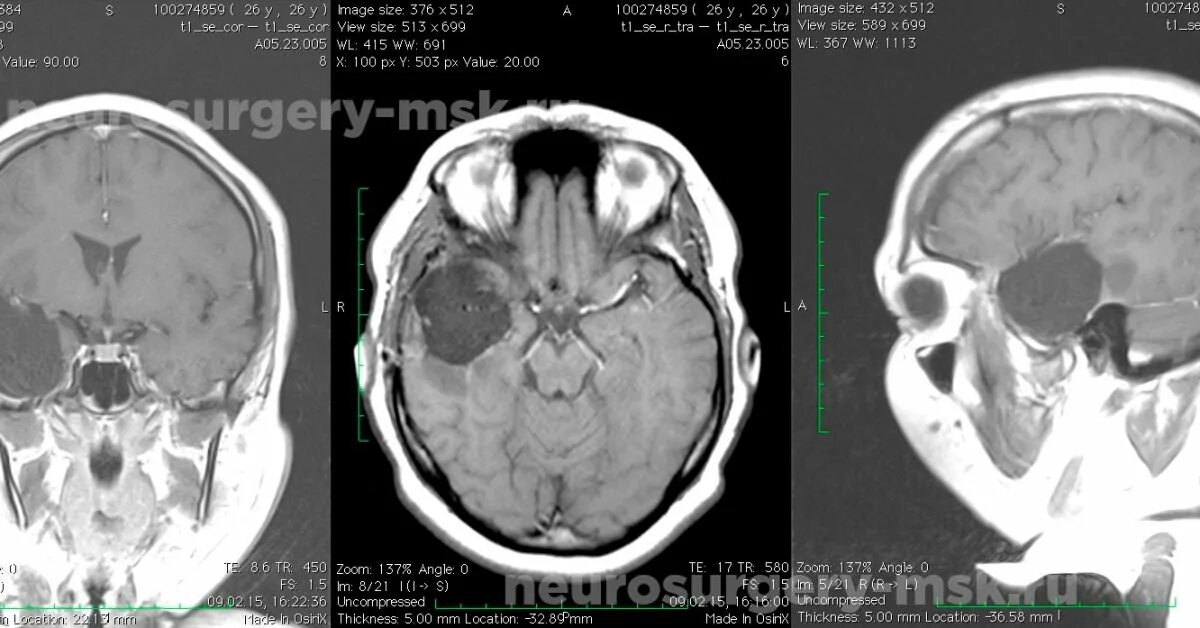

Астроцитома головного мозга прогноз после операции